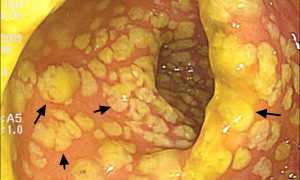

Выполнение фиброэзофагогастродуоденоскопии (ФГДС) является обязательным для постановки правильного диагноза. Метод позволяет с высокой точностью визуализировать изменения слизистой оболочки верхних и средних отделов пищеварительного тракта. Можно увидеть степень поражения эпителия, характер распространения патологии, наличие дефектов на поверхности тканей, осложнения в виде кровотечения, пенетрации, перфорации, инородные тела.

Диагностику выполняют с помощью прибора — эндоскопа со световым диодом и камерой. Трубку аппарата вводят через ротовую полость. По мере продвижения на экране отображаются структуры ЖКТ. У взрослых дополнительно проводят взятие биоптатов для гистологического исследования.